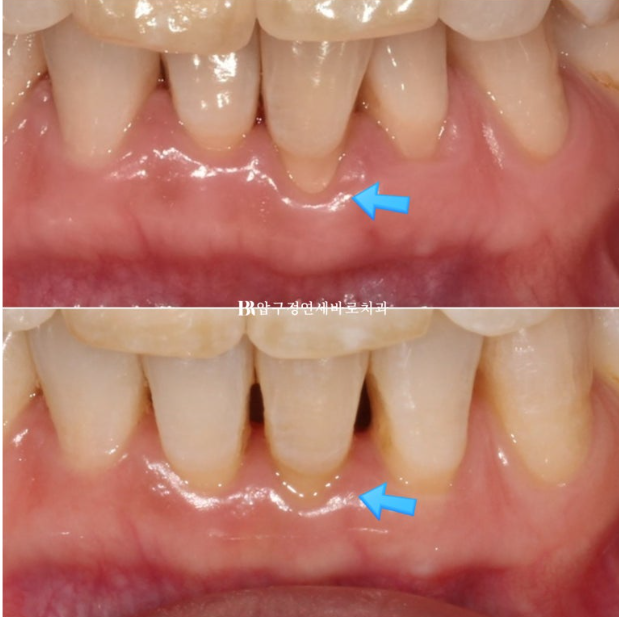

파란 화살표 부분은 잇몸이 주변치아에 비하여 내려가 있습니다.

그 이유는 배열에서 가장 벗어난 치아여서 입니다.

제자리로 넣어주면 잇몸이 회복되기도 합니다.

배열에서 가장 많이 벗어난 덕분에 잇몸이 유독 내려갔던 치아를 자세히 보겠습니다.

23.07~24.05

잇몸 퇴축이 회복이 되면서 치아뿌리 노출이 줄었습니다.